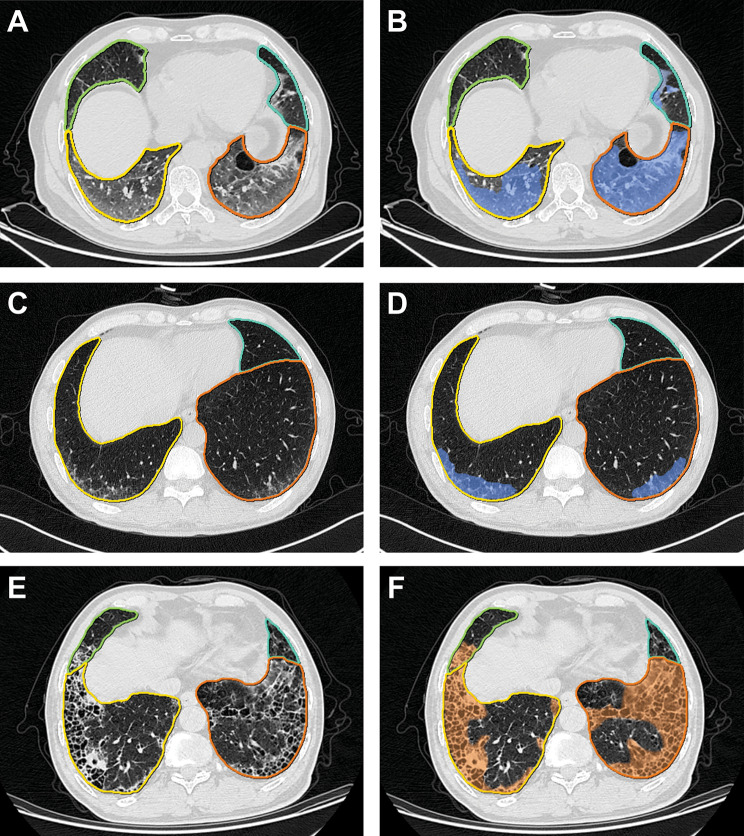

Analysis of pretreatment CT images by using the dedicated multitask deep learning algorithm developed for pulmonary pneumonia (Beijing Deepwise & League of PhD Technology Co. Ltd, China) [28]. Further information regarding this approach is reported in the Supplementary Methods (Supplementary Material 1). Fig. 2 shows examples of pulmonary lobe and opacity segmentation. First, we segmented each lung lobe and the bilateral lungs and calculated the volume. Subsequently, fibrosis lesions were labeled by radiologists, while the GGO and consolidation lesions in the corresponding lobes were labeled using the well-trained artificial intelligence (AI) algorithm, and then the volume of each lesion was computed. All opacity pieces extracted by the AI system were checked by a radiologist (J.Z.) to prevent lung cancer lesions from being labeled. The lesion volume percentage in each lobe as well as the number of involved lung lobes were calculated. ILA determined by AI was defined as the sum of GGO and fibrosis extent affecting more than 5% of any lung zone.

Fig. 2.

Examples of pulmonary lobe segmentation and opacity segmentation (A, B), pretreatment CT images of a patient with ground glass opacity, the patient developed grade 3 CIP at 133 days after ICI treatment. (C, D), pretreatment CT images of a patient with ground glass opacity, the patient developed grade 1 CIP at 118 days after ICI treatment. (E, F) pretreatment CT images of a patient with fibrosis, the patient did not develop CIP after ICI treatment

Multivariate logistic regression analysis using backward stepwise model selection showed that the AI-evaluated percentage GGO extent was an independent predictor of the presence of grade ≥ 2 CIP (odds ratio (OR), 1.446; 95% confidence interval (CI): 1.103–2.257, P = 0.045) after adjustment for age and histology. Preexisting GGO extent in the right lower lung (OR, 1.157; 95% CI: 1.055–1.341, P = 0.009) and histology (OR, 4.734; 95% CI: 1.502–18.379, P = 0.012) were independent predictors of the existence of high-grade CIP. Compared with patients without high-grade CIP, patients with high-grade CIP were more likely to have a larger GGO extent in the right lower lung before ICI treatment. Fig. 2 shows typical cases. To enhance the clinical interpretability of the results, we evaluated the GGO extent as both a continuous and categorical variable, as shown in Table S3. As the findings from the analyses based on binary and continuous variables were consistent and more readily interpretable, binary GGO extent was employed in constructing both Model 1 and Model 2 in subsequent analyses. The optimal cutoff value for GGO extent was determined to be 1.01% after adjusting for histology and age, while the optimal cutoff value for preexisting GGO extent in the right lower lung was found to be 2.55% after adjusting for histology.